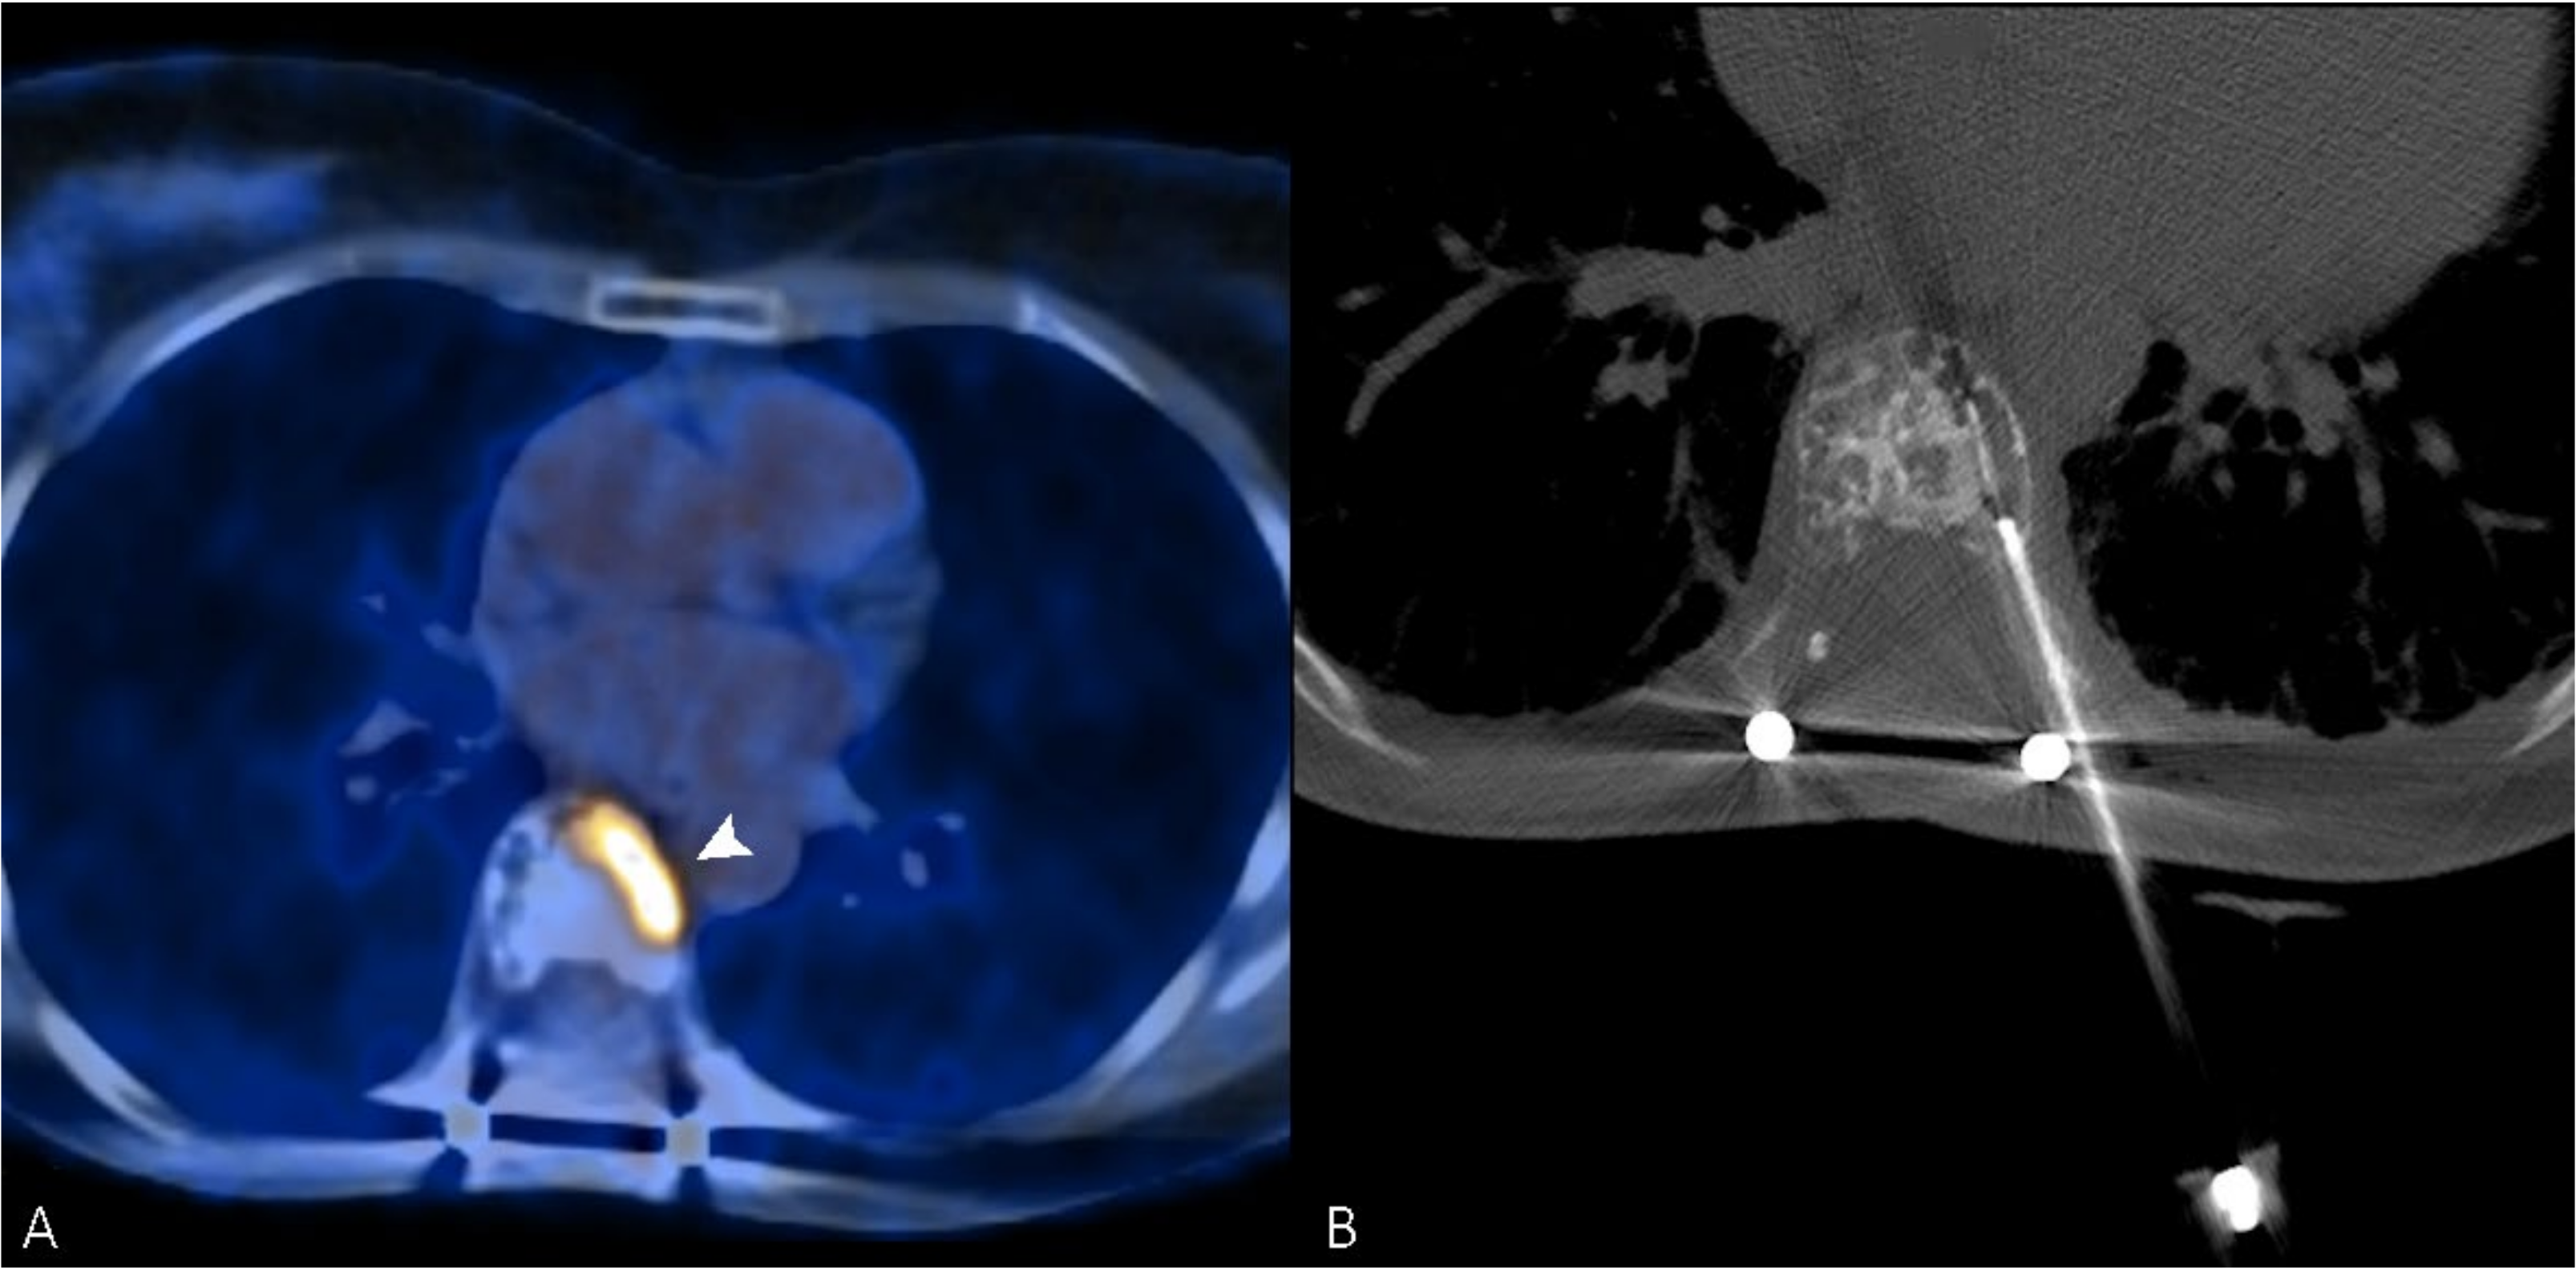

Figure 2.

(A) PET/CT scan of a 56-year-old woman, which shows an intense uptake of 18F-FDG in correspondence with a painful vertebral metastasis from breast cancer in the body of T7 (arrowhead). (B) Radiofrequency ablation of the lesion performed through a transcostovertebral approach.